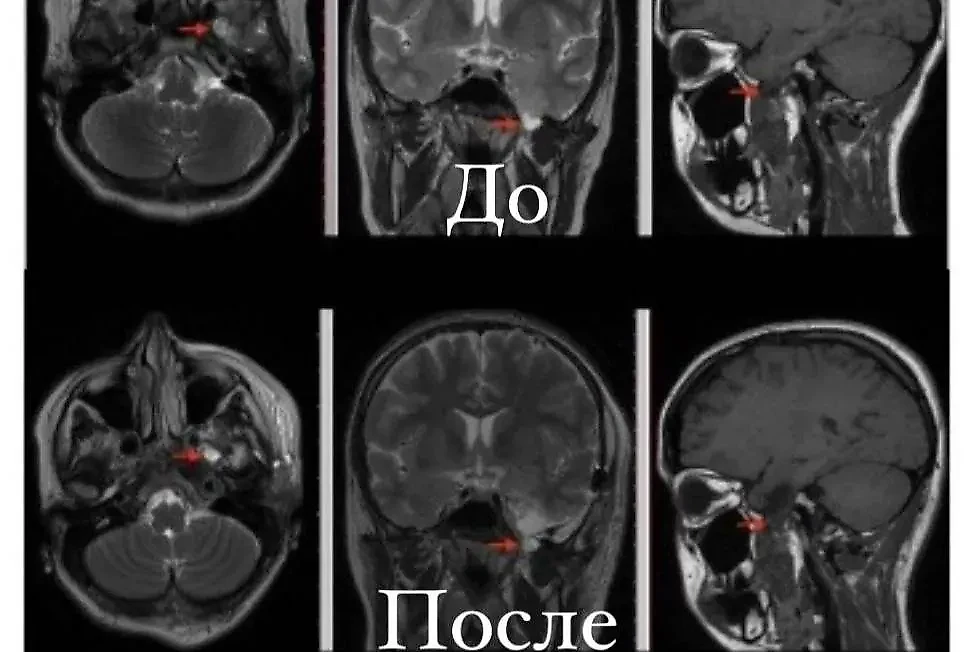

С регулярными приступами эпилепсии поступила 17-летняя пациентка в центр на Авангардной. После нескольких МРТ головного мозга нейрохирурги выявили редкую патологию. Девушке диагностировали височное базальное энцефалоцеле — это врождённое заболевание, вариант "скрытой" мозговой грыжи, приводящее к приступам эпилепсии, которые не поддаются медикаментозному лечению. Выяснилось, что это редкая аномалия, в мире известно только примерно 40 таких случаев.

"Семья девочки выбрала хирургическое лечение. При этом виде лечения достигаются хорошие долгосрочные результаты контроля эпилептических приступов, и более 75% пациентов излечиваются от них в долгосрочной перспективе", — говорится в сообщении Комитета по здравоохранению Санкт-Петербурга.

Операция прошла успешно, самочувствие пациентки стабильное. Теперь девушка готовится к скорой выписке и возвращению к повседневной жизни.